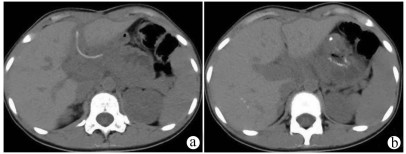

A preliminary study on percutaneous transhepatic drainage combined with sequential percutaneous nephroscopy in treatment of refractory liver abscess

Changhu DUAN, Xiaochen LIU, Jianlong DING, Jianfeng DUAN, Xirong ZHAO, Fan YANG, Ling WU, Lifei ZHAO, Sheng TAI

2021, 37(11): 2622-2625. DOI: 10.3969/j.issn.1001-5256.2021.11.026

Abstract(1123) HTML (227) PDF (2925KB)(75)

Abstract:

Objective  To investigate the clinical effect of percutaneous transhepatic drainage combined with sequential percutaneous nephroscopy for necrosectomy and drainage in the treatment of refractory liver abscess after transcatheter arterial embolization (TACE).  Methods  A retrospective analysis was performed for three patients with refractory liver abscess after TACE in The Affiliated 3201 Hospital of Xi'an Jiaotong University School of Medicine from January 2018 to December 2020, and among the three patients, one had the formation of liver abscess after TACE for hepatic metastases after pancreaticoduodenectomy, one had liver abscess after repeated TACE for massive hepatocellular carcinoma, and one had secondary liver abscess after TACE for traumatic hepatic rupture. All three patients received percutaneous transhepatic drainage and sequential percutaneous nephroscopy for the treatment of refractory liver abscess, and their specific treatment process was summarized.  Results  All three patients were diagnosed with refractory liver abscess based on CT, routine blood test, procalcitonin, blood culture, and clinical manifestation. Percutaneous transhepatic catheterization under the guidance of conventional ultrasonography or CT and effective antibiotics had an unsatisfactory therapeutic effect, and after sequential percutaneous nephroscopy was performed for necrosectomy and drainage, liver abscess was cured and the patients had good prognosis.  Conclusion  For refractory liver abscess after TACE, when routine puncture treatment has an unsatisfactory therapeutic effect or a patient cannot tolerate surgical operation, percutaneous transhepatic drainage combined with sequential percutaneous nephroscopy is safe and effective in the treatment of refractory liver abscess.